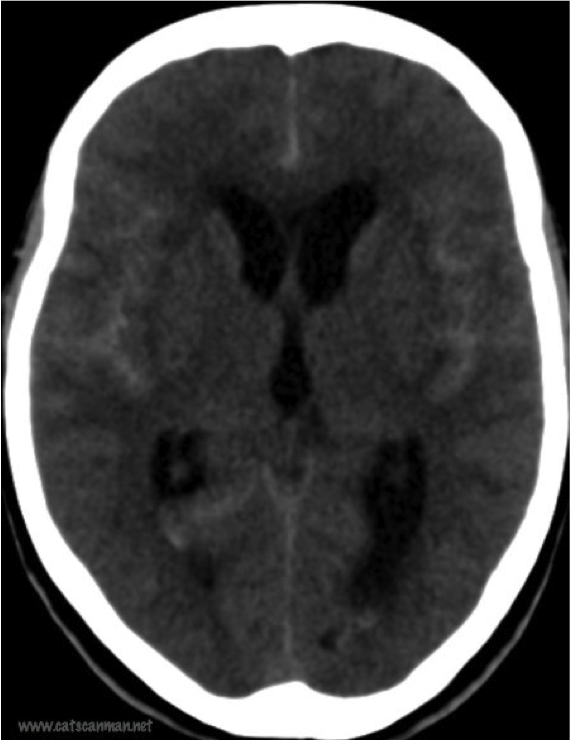

What is shown?

Subarachnoid hemorrhage